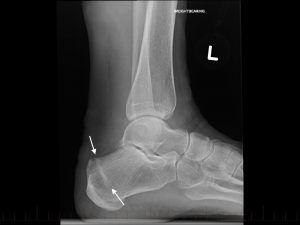

Son fracturas que ocurren generalmente en los pies, producen dolor crónico localizado en un punto, alivian en reposo, aumenta el dolor al caminar o apoyar la zona afectada.

Se puede sospechar el diagnóstico al examinar al paciente y escuchar su historia clínica, Las Rx en algunas ocasiones pueden mostrar la lesión, pero generalmente pasan desapercibidas en los primeros días de los síntomas. La RESONANCIA MAGNÉTICA es el exámen más preciso que puede revelar la lesión y confirmar el diagnóstico que se sospecha.